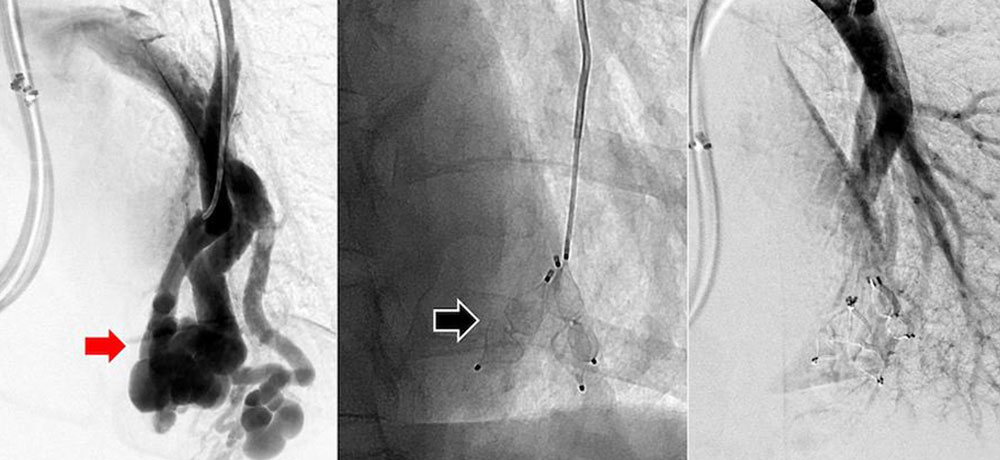

Liquid embolic agent ethylene vinyl alcohol (EVOH) copolymer

Ethylene vinyl alcohol (EVOH) copolymer is available as a mixture with dimethyl sulfoxide (DMSO) and micronized tantalum. The added tantalum ensures extremely good fluoroscopic visibility throughout the entire intervention. Upon injection through a microcatheter and contact with blood, DMSO diffuses out of the mixture, resulting in very slow, controlled precipitation of EVOH. The result is a viscous and coherent lava-like mass that can be modeled for many minutes. EVOH is mainly used in the treatment of complex arteriovenous malformations. By means of the so-called “plug-and-push” technique, the complete nidus can often be embolized from one catheter position. Since DMSO leads to irritation of the vessel wall, pain during the injection is not uncommon. It is therefore recommended that complex embolizations with EVOH be performed under general anesthesia.